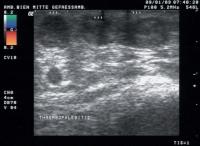

Duplexsonographie - Thrombophlebitis

Abbildung 13: Thrombosiertes oberflächliches Venenkonvolut, erweitertes Venenlumen, fehlende Komprimierbarkeit, keine Farbkodierung

Keywords: DuplexsonographieThrombophlebitisThrombusVene